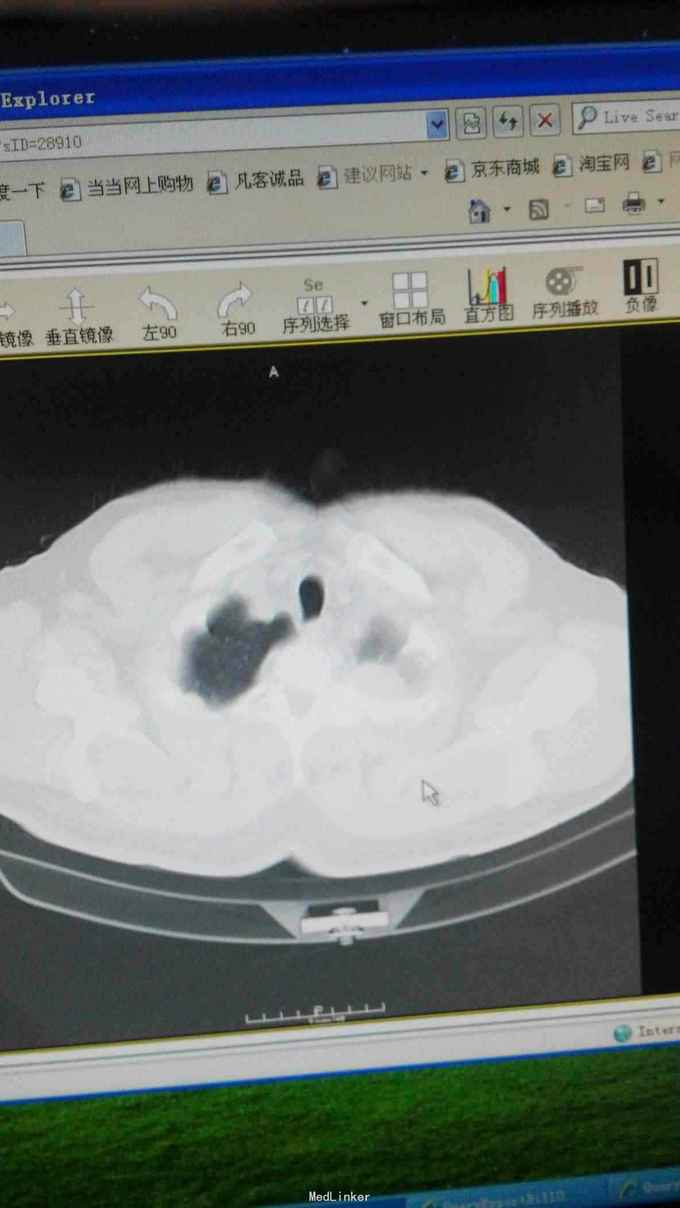

左肺癌化疗后,2015年7月行细胞免疫治疗及粒子植入术

50天复查